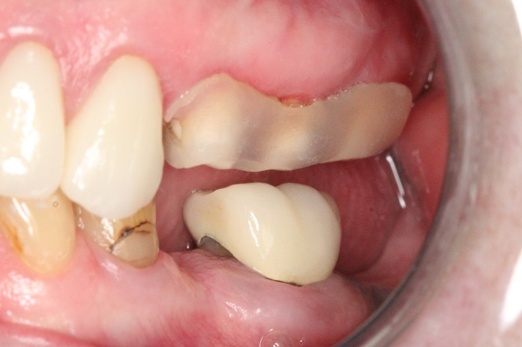

Figure 10 through Figure 13 show the preoperative x-ray and the sequence of beginning with healed sites through the surgical placement of the implants. The implants were protected by an Essix-style wound-protection removable retainer for approximately 12 weeks. After the integration phase, the implants and the natural dentition were prepared using traditional crown-and-bridge high-speed diamond and zirconia cutting burs to remove decay and existing restorative materials, to complete and refine the natural-tooth structures to receive full-crown coverage, and to prepare and refine gingival margins of the zirconia implants where needed.

Fig 11. Preoperative healed sites.

Figure 11

Fig 12. Ceramic implants placed and sutured.

Figure 12

Fig 13. Lateral view after placement.

Figure 13